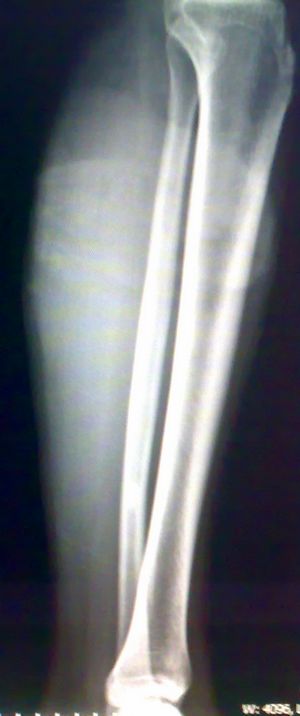

标题: X7846:M 20岁 外伤来诊。良性骨肿瘤吗? [打印本页]

标题: X7846:M 20岁 外伤来诊。良性骨肿瘤吗?

考虑腓骨下段良性骨肿瘤或骨肿瘤样病变(软骨瘤?);建议行mri检查。

腓骨中下段骨皮质下不规则高密度影,侧位呈水滴形。外伤,估计平时没有症状,结合病人年龄,支持纤维性骨皮质缺损